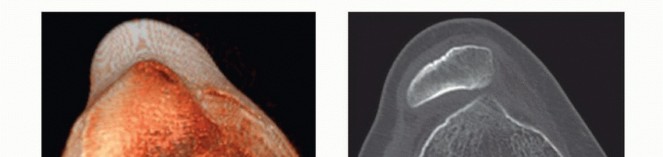

DEFINITION Trochlear dysplasia is a pathologic condition occurring in approximately 3% of the population but …